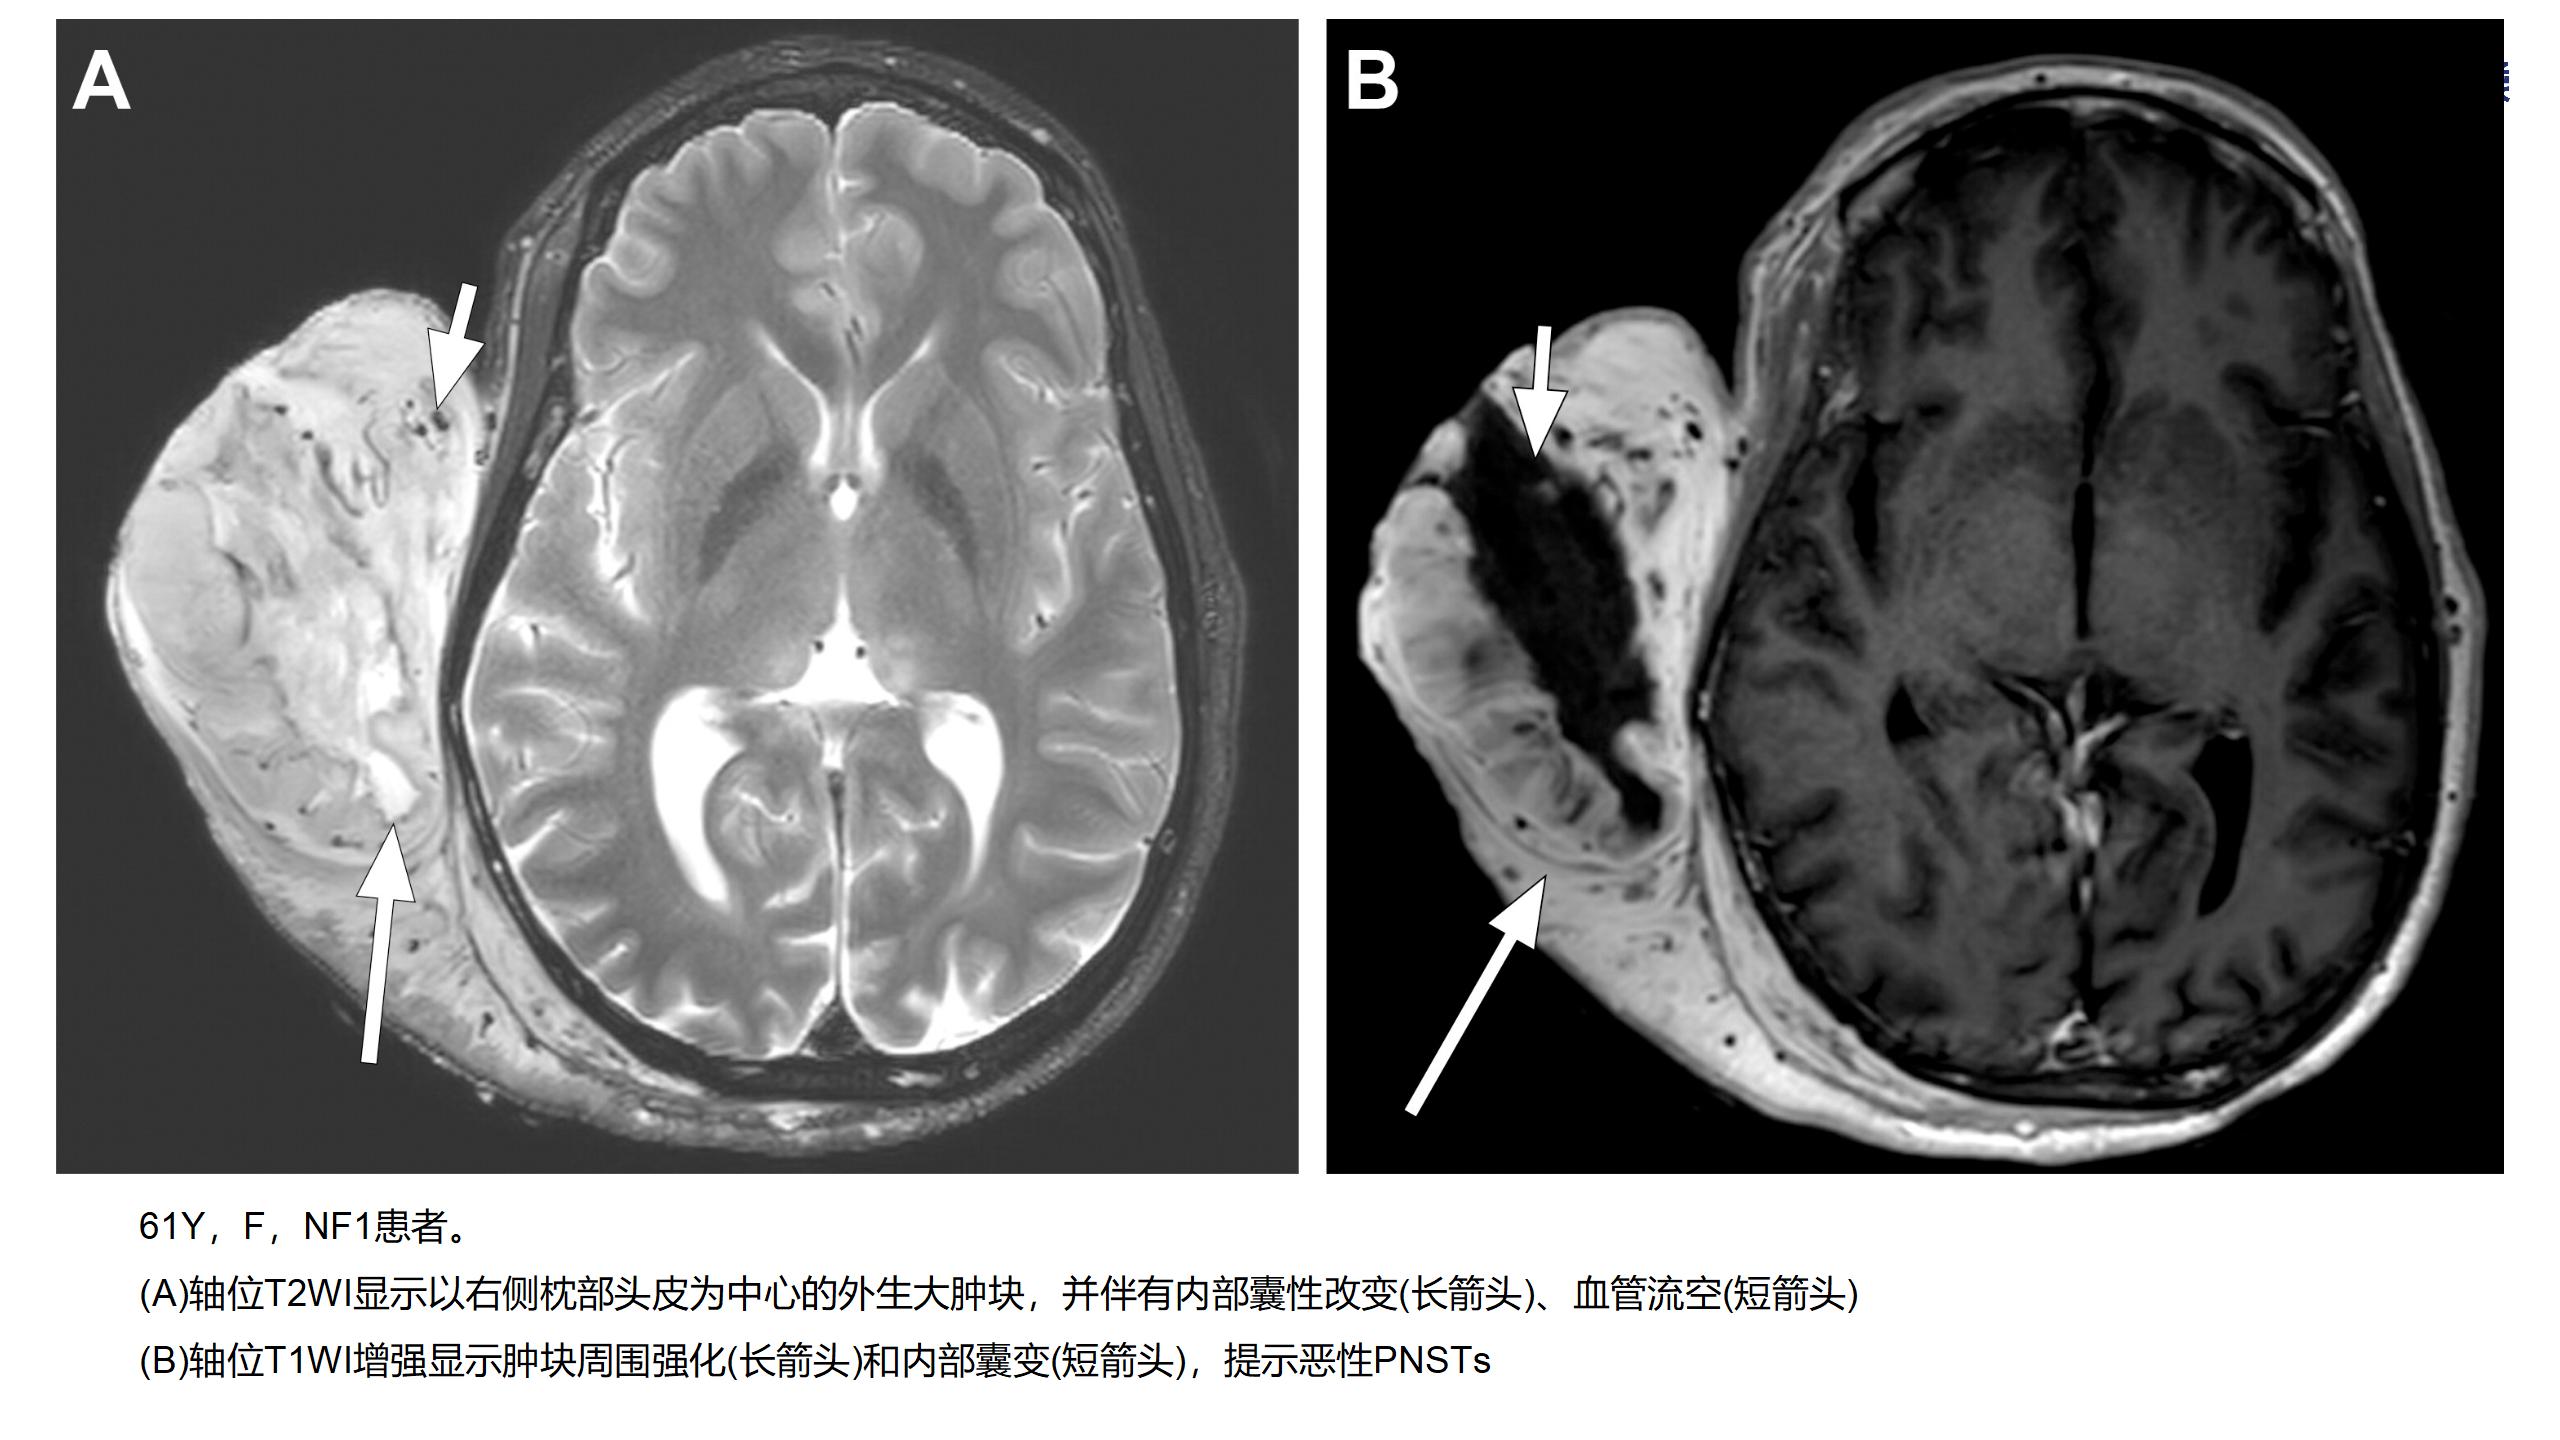

神经纤维瘤病(NF1)